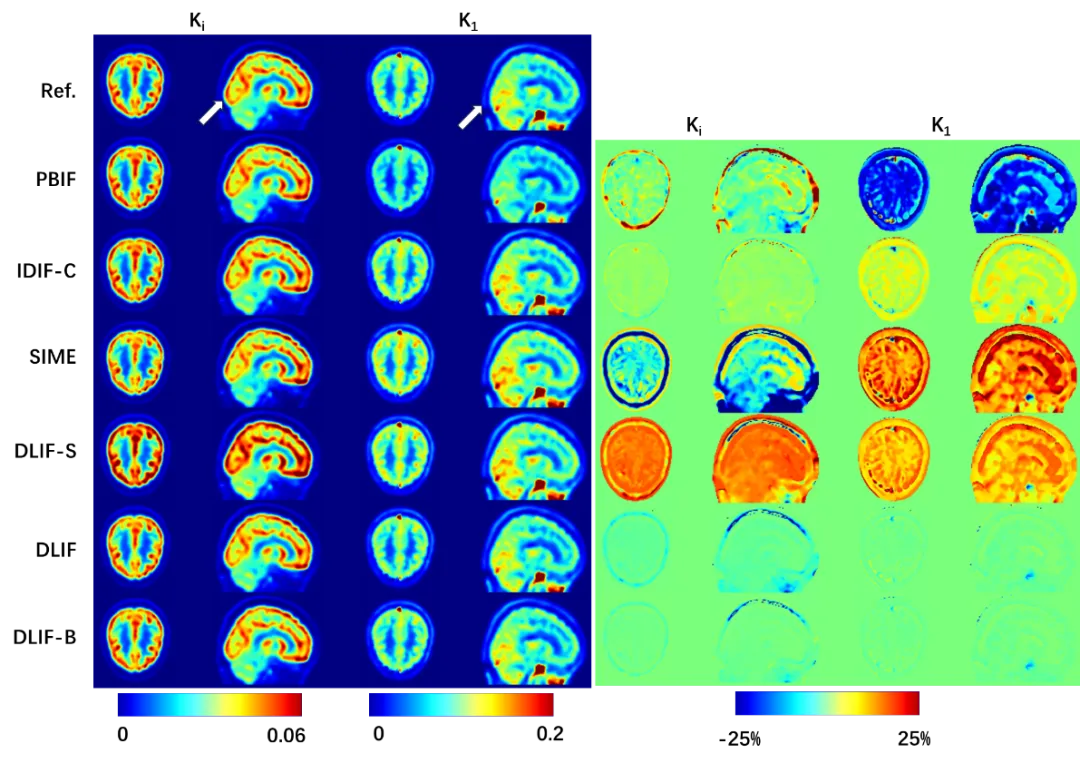

从视觉和定量两个方面来看,参数图像也与参考图像高度吻合(图3)。这些结果证实了无创且准确地估计血流输入函数的可行性,该方法适用于常规的短视野或专用脑部扫描PET系统,并且无需进行部分容积校正。通过精准计算获得的全局灌注、净流入、净代谢和其他微观参数,有助于推动在广泛的神经和精神疾病中大脑代谢功能的研究,进而辅助制定更有效的治疗策略。

图3 展示了使用不同方法估计的输入函数所计算的K1/Ki图像(左)。可以观察到,使用所提出的方法(DLIF)估计的参数图像与参考图像最为接近,且误差值范围最小(右)。